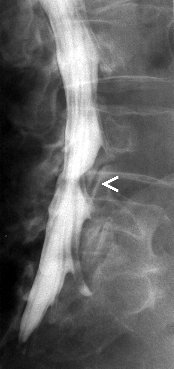

Myelografie

Myelografie is het in beeld brengen van het ruggenmergkanaal door middel van een cotrasmiddel. Deze wordt door middel van een punctie ingespoten in de duraal zak in de lage rug. Er wordt dus in de rug geprikt zodat een naald door kan schuiven tussen de wervels tot in het ruggenmergkanaal. Dit kan gebeuren onder plaatselijke verdoving, maar dit is geen regel. Gesteld wordt dat er in elk geval moet geprikt worden. Er kunnen opnames genomen worden ter hoogte van de hals, borst of lage rug. Na de punctie worden er conventionele opnames gemaakt waarna de patiënt naar de CT-scan wordt gebracht om axiale beelden te maken in de regio waar zich mogelijk problemen voordoen.

Het is echter zo dat deze onderzoek steeds vaker vervangen wordt door een MRI vande rug, daar dit minder invasief is, minder risicos inhoudt en beter verdragen wordt door de patiënten.

Indicaties:

Het opsporen van een degeneratieve tussenwervelschijf

Tumoraal proces tussen de wervels

Trama met fractuur of verplaatsing van een wervel

Post opperatieve problemen